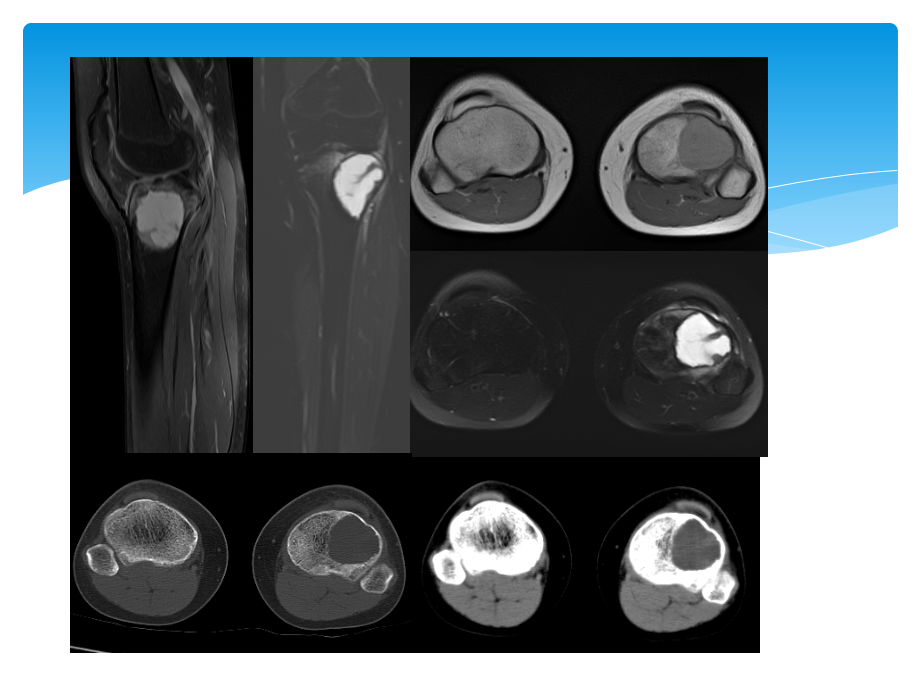

,单击此处编辑母版标题样式,*,*,单击此处编辑母版文本样式,第二级,第三级,第四级,第五级,15岁,女,01142857,摔伤致左膝痛2-3月,胫骨软骨母,12岁,男,,软骨母细胞瘤的影像诊断,福建医科大学附属第一医院影像科-李玉萍,2015.07.10,软骨母细胞瘤认识发展史,1923年Ewing-钙化的巨细胞瘤。,1927 年 Kolodny-含有软骨的巨细胞瘤。,1931 年 Codman-骨骺软骨源性巨细胞瘤。,1942年 Jaffe和Lichtenstein-成软骨细胞瘤或软骨母细胞瘤(CB Chondroblastoma)。,临床表现,90%的CB患者发病年龄为5 25岁。,临床症状缺乏特异性,以疼痛最常见。30%患者可表现为类似滑膜炎的关节症状。,少数CB具有侵袭性行为,极少数病例甚至有肺转移。,起源及病理,CB的起源存在一定争议。目前多认为起源于软骨细胞的前体,起源于青少年长管状骨骨端和骨骺。,镜检成分为软骨母细胞、基质及多核巨细胞。,单核软骨母细胞免疫酶标记S一100蛋白阳性。,影像表现1,部位:多发生于长骨骨骺或骨突部、中心或稍偏心,极少数病灶可突破骨端进入关节。发病部位以股骨(33%)、肱骨(20%)和胫骨(18%)等长管状骨最常见,近一半发生于膝关节周围,少数可位于手足等不规则骨。,境界:CB多呈境界清楚的溶骨样骨质破坏,长管状骨的骨质破坏多呈圆形,CB境界清楚,多数可见明显硬化边,少数伴有不太宽的硬化带,一方面与肿瘤缓慢生长,刺激邻近成骨细胞有关,也可能为肿瘤边缘钙化所致。极少数发展较快的肿瘤缺乏硬化带或硬化边缘。硬化边的存在对于鉴别诊断很有价值,因为绝大多数骨巨细胞瘤缺乏硬化边,外形:CB内软骨成分常形成软骨小叶状改变,病灶边缘常因此而呈结节状突起;CB瘤骨界面呈扇贝状或花边状,病理基础反映软骨小叶对正常骨结构的挤压。,影像表现2,钙化:25%50%的CB病灶内部可见钙化,位于软骨小叶间隔的钙化呈直径1 2cm的环状、弓状,具有定性诊断价值;位于小叶内的钙化呈斑点或雀斑状,无序排列,无诊断特异性。,骨膜反应、软组织反应:伴随炎症反应。,30%50%的CB引起骨膜炎,导致骨膜增生,10%增生范围广泛、致密、粗厚,成层并与骨干平行。具有鉴别诊断价值。30%的CB有关节腔积液。CT和MRI上相对常见,X线平片则少见。,CASE1:男,13岁,左侧小腿疼痛半年,冻后及冻余石蜡报告:,(左胫骨上段病变)软骨母细胞瘤伴骨化。,CASE2:男,18岁,右膝发热3个月。右胫骨上段软骨母细胞瘤。S-100(+)。,CASE3:,20岁,男。,肱骨上段软骨母细胞瘤,CASE4:男,38岁,左髋部疼痛1年,左股骨头软骨母细胞瘤,CASE4:男,29岁,右大腿酸痛2年余,病理:符合软骨母细胞瘤,伴动脉瘤样骨囊肿。S-100(+),鉴别诊断-,骨巨细瘤,左胫骨骨巨细胞瘤,15岁,女,01142857,摔伤致左膝痛2-3月,胫骨软骨母,12岁,男,,软骨母细胞瘤。,骨巨细胞瘤:年龄、偏侧,体积较大,密度较低,分隔嵴突、硬化边不清,周围组织炎症反应较轻,,软骨母细胞瘤:偏中心,较小,无分隔、内见弧形钙化、密度较高,可有硬化边、硬化带,周围炎症反应较明显。,鉴别诊断-,内生软骨瘤,女,3岁,鉴别诊断-,骨结核,女,3岁,左胫骨结核,鉴别诊断-,动脉瘤样骨囊肿,典型软骨母细胞瘤影像诊断,5-25岁,长骨骨骺、骨突、可跨越骨骺,溶骨性破坏,硬化边可见,内可有弧形钙化,部分周围伴炎症改变,谢谢大家,